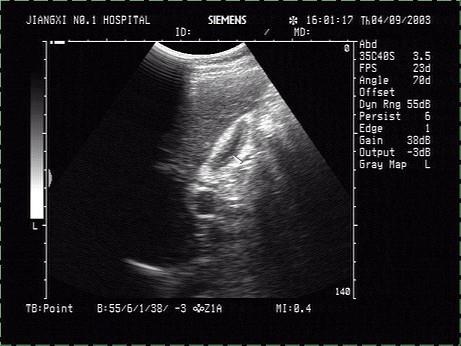

男,餐后半小时行B超检查。图中箭头所示器官最可能是?(?)A.餐后胆囊B.胃C.十二指肠D.门静脉E.肝圆韧带

问题 男,餐后半小时行B超检查。图中箭头所示器官最可能是?(?)

选项 A.餐后胆囊 B.胃 C.十二指肠 D.门静脉 E.肝圆韧带

答案 A